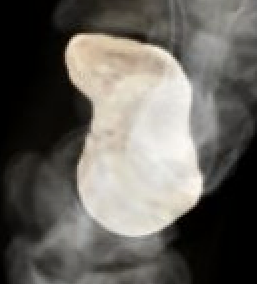

Anatomy

Scaphoid is greek for boat

- shaped more like a twisted peanut

- majority is articular cartilage except for dorsal ridge

- dorsal ridge is site of entry of majority of blood supply